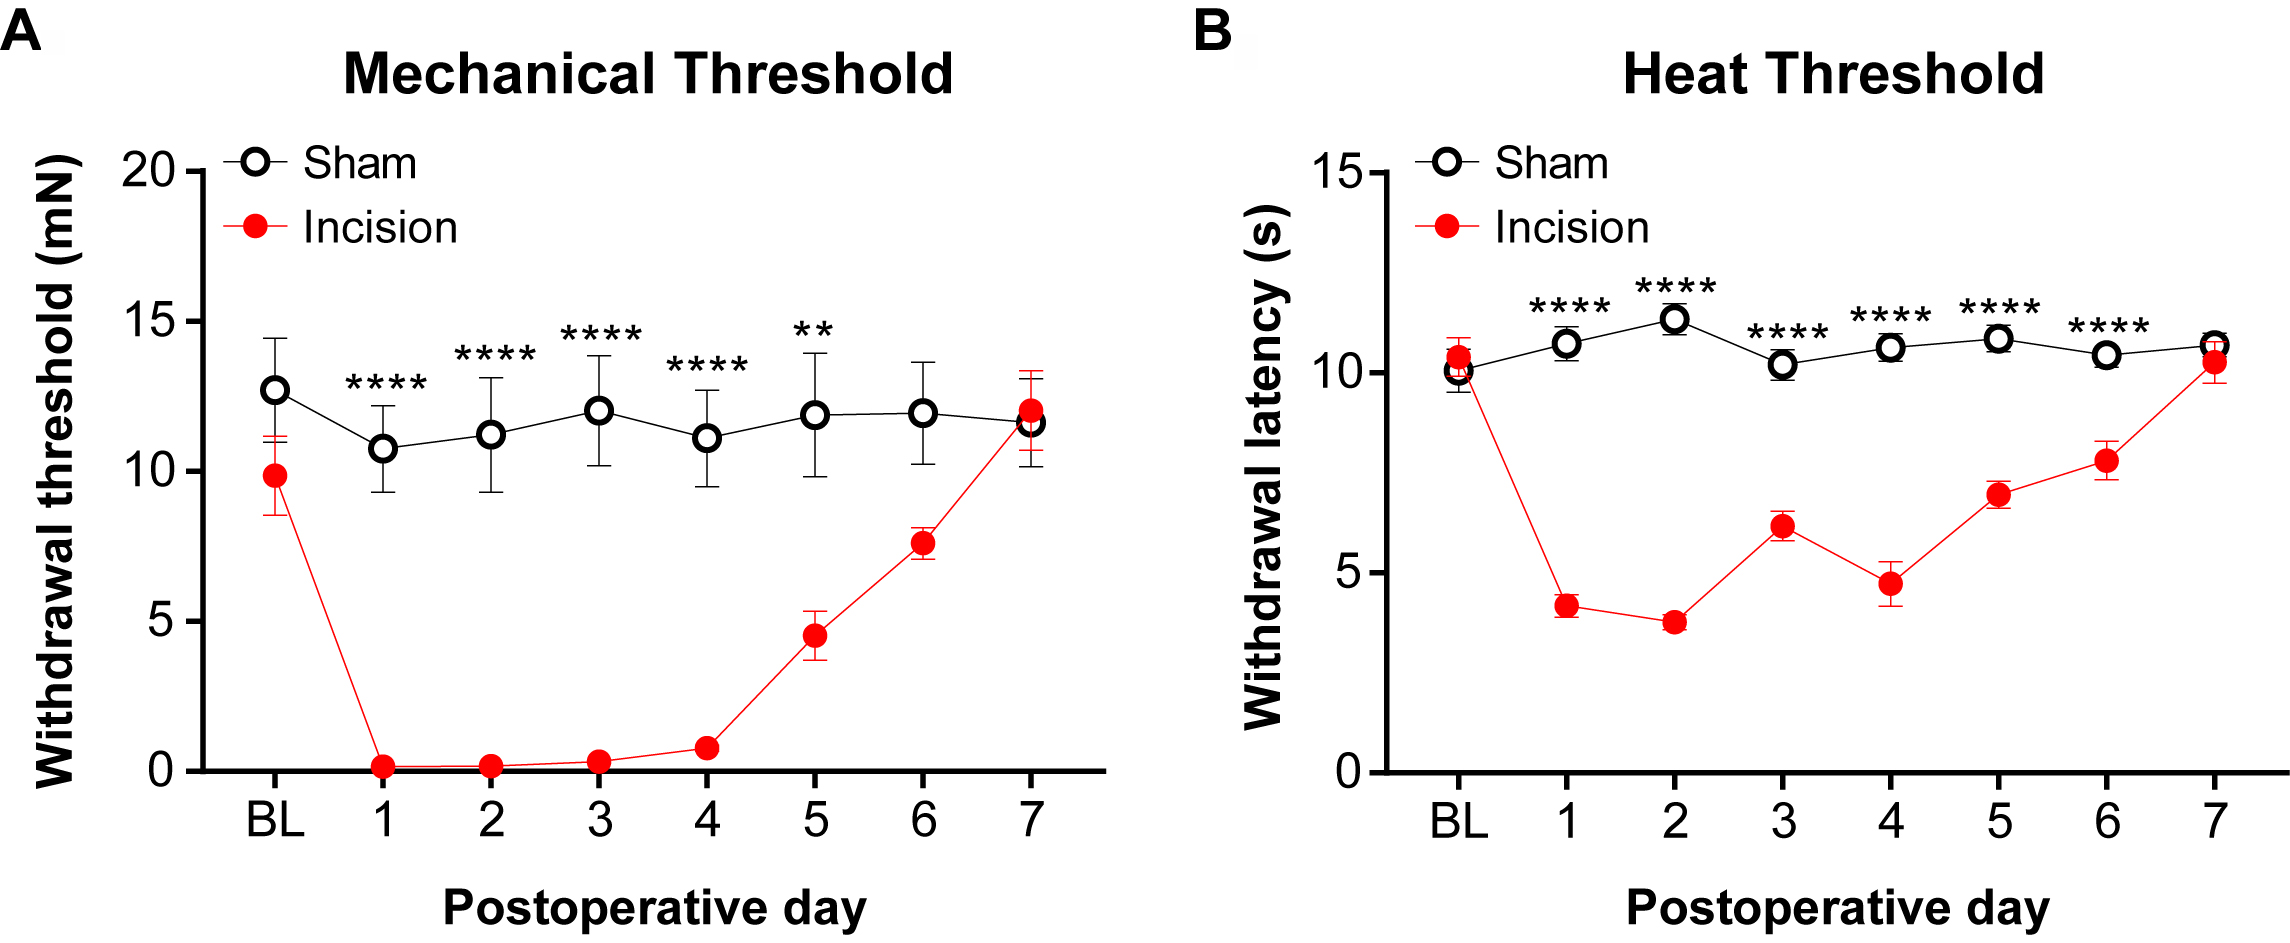

Statistical significance was determined with GraphPad Prism 7 Software and graphs are shown as mean ± SEM. A two-way ANOVA with a Sidak post-hoc was used to determine statistical significance for mechanical and heat thresholds. A complete description of statistics used for analyzing mechanical and heat threshold behavioral data is provided in Cowie et al. (2018).

- For consistent behavioral results, apply mechanical and heat stimuli to the medial-posterior aspect of the plantar hindpaw (Figure 9). This area is the least sensitive at baseline because the heel is weight bearing whereas other areas near the pads are more sensitive and variable in withdrawal threshold. Therefore, using the heel area that provides a consistently high baseline withdrawal threshold allows for the best detection of change due to incision (Brennan et al., 1996). Mice were acclimated for 1 h in Plexiglass chambers placed on either a mesh platform (mechanical threshold) or glass platform (heat threshold). Calibrated von Frey monofilaments (0.09 to 19.6 mN) were applied to the plantar hindpaw and the withdrawal threshold for each animal was calculated using the up-down method (Dixon, 1980; Chaplan et al., 1994). The Hargreaves assay was used to measure heat sensitivity as previously established (Hargreaves et al., 1988; Jackson et al., 1995; Barabas and Stucky, 2013; Cowie et al., 2018). Withdrawal latencies to a focused radiant heat source (IITC, Life Sciences Instruments) underneath the glass platform were measured 3 times and averaged for each mouse. A cutoff of 20 s was used to avoid injury. Examples of mechanical and heat hypersensitivity following incision are shown in Figure 10.

Figure 10. Mechanical and heat thresholds following incision. A. von Frey monofilaments was applied to most sensitive location following incision and the Dixon up-down method (Dixon, 1980) was used to determine mechanical threshold. B. The Hargreaves assay (Hargreaves et al., 1988) was used to measure the withdrawal threshold in response to a radiant heat source that was applied to the most sensitive location following incision. These data were modified from Cowie et al. (2018). Data shown as mean ± SEM, repeated-measures two-way ANOVA and Sidak post-hoc analysis, **P < 0.01 and ****P < 0.0001 sham versus incision. For (A) and (B), n = 8 male mice per group.